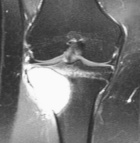

22 year old female with two month history of right knee pain

Zoom image: Radiological image Radiological image.